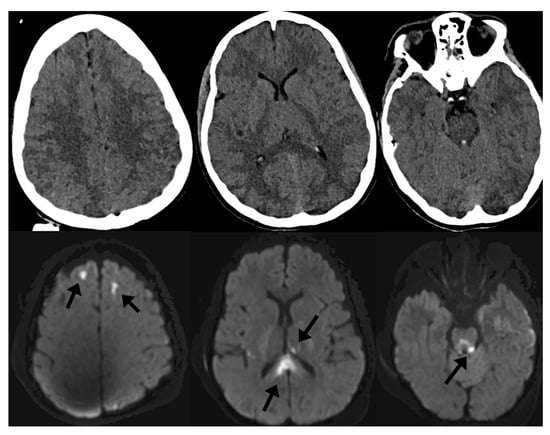

In the setting of TBI, specific conventional MRI sequences such as diffusion-weighted imaging (DWI) and susceptibility-weighted imaging (SWI) tend to be helpful in understanding the clinical implications of injury. In moderate-to-severe TBI, it is common to identify small, scattered microhemorrhages within the brain parenchyma after injury. These microhemorrhages, when localized to the gray–white junctions or white matter tracts, are associated with diffuse axonal injury (DAI). DAI has been extensively studied in the clinical—and less so the pathological—literature and is a negative prognostic factor in recovery from TBI [5,10,11,12,13,14,15,16,17,18]. Often, microhemorrhages related to shear injury are invisible on noncontrast CT because of limited tissue contrast with CT as well as dose reduction limitations in humans and associated noise. However, DWI and SWI sequences of MRI are sensitive enough to detect such small areas of cytotoxic edema and microhemorrhage and are high-sensitivity markers of DAI. Figure 1 demonstrates this phenomenon, where punctate microhemorrhages are difficult to visualize on head CT but are readily apparent on SWI. For this reason, MRI has become an important adjunctive imaging modality in cranial neurotrauma as a means to prognosticate on the expected cognitive and behavioral outcomes of patients [19].

Figure 1.

Noncontrast computed tomography (CT) of the head (top row) and diffusion-weighted imaging (DWI) of the brain (bottom row) of the same patient after traumatic brain injury (TBI). Imaging markers of diffuse axonal injury (DAI) include microhemorrhages on susceptibility-weighted imaging (SWI) as well as focal areas of cytotoxic edema on DWI (arrows) that are not visible on CT.